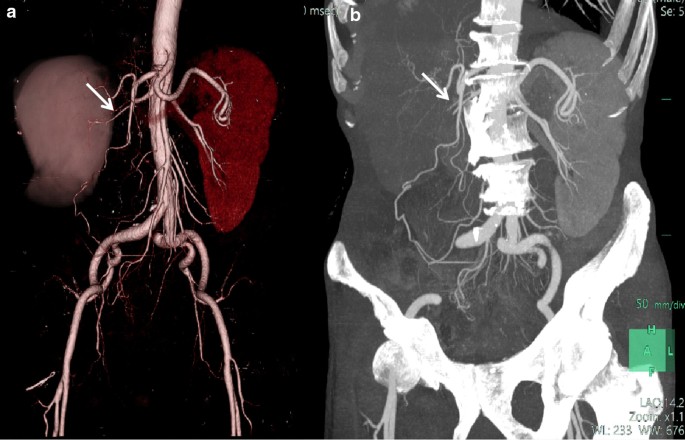

CTA reconstruction of eight (61.5%) cases of CDC did not detect arterial enlargement or new tumor vessels. In seven (53.8%) cases, renal artery branches within tumors were attenuated or sparse (Fig. 5). Abnormal venous drainage was not observed in any of the cases.

Local invasion and distant metastasis

In nine of thirteen (69.23%) cases, CT images showed evidence of intra-abdominal metastatic disease (Table 1). Perirenal infiltration is common in renal CDC. In this group, perirenal fat blurring or prerenal fascia thickening was observed in 12 (92.3%) cases. Direct invasion as peritoneal and lymphatic metastasis was observed in nine (69.2%) cases (Fig. 7a, b). In seven cases, the metastases surrounded the renal artery and caused renal artery stenosis (Fig. 5a, b). Adrenal gland involvement was observed in two (15.4%) cases and included the left side in one case and bilateral involvement in one case. Inferior vena cava involvement was observed in one (7.7%) case. There were three (23.1%) cases of bilateral lung metastasis, one (7.7%) case of bilateral pleural metastasis, one (7.7%) case of brain metastasis, and one (7.7%) case of bone metastasis (right ribs, right pubic symphysis, and left scapula).

In present study, CTA showed that the renal artery was involved in the blood supply and the distal branches were destroyed. The filling defect was observed in the renal vein and inferior vena cava. The tumor thrombus showed an expanded shape and the degree of enhancement was similar to that of the central necrotic and the hypovascular areas. No tumor blood vessels were observed in the vicinity of the tumor, and the original renal blood vessels were not thickened or significantly displaced. These characteristics indicate that CDC tumor cells do not produce angiogenic factors, and the original renal artery branches are rarely destroyed by tumor cells. The fibrous tissue in the tumor stroma can compress the intratumoral vessels; this differs from renal tubular cell carcinoma, which is characterized by vessel hyperplasia and a spherical shape of tumors.